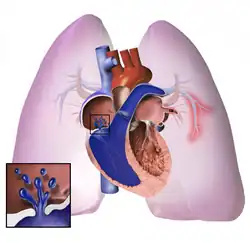

The pathogenesis of pulmonary arterial hypertension (WHO Group I) involves the narrowing of blood vessels connected to and within the lungs. This makes it harder for the heart to pump blood through the lungs, as it is much harder to make water flow through a narrow pipe as opposed to a wide one. Over time, the affected blood vessels become stiffer and thicker, in a process known as fibrosis. The mechanisms involved in this narrowing process include vasoconstriction, thrombosis, and vascular remodeling (excessive cellular proliferation, fibrosis, and reduced apoptosis/programmed cell death in the vessel walls, caused by inflammation, disordered metabolism and dysregulation of certain growth factors).[27][28] This further increases the blood pressure within the lungs and impairs their blood flow. In common with other types of pulmonary hypertension, these changes result in an increased workload for the right side of the heart.[16][29] The right ventricle is normally part of a low pressure system, with systolic ventricular pressures that are lower than those that the left ventricle normally encounters. As such, the right ventricle cannot cope as well with higher pressures, and although right ventricular adaptations (hypertrophy and increased contractility of the heart muscle) initially help to preserve stroke volume, ultimately these compensatory mechanisms are insufficient; the right ventricular muscle cannot get enough oxygen to meet its needs and right heart failure follows.[16][28][29] As the blood flowing through the lungs decreases, the left side of the heart receives less blood. This blood may also carry less oxygen than normal. Therefore, it becomes harder and harder for the left side of the heart to supply sufficient oxygen to the rest of the body, especially during physical activity.[30][31][11] During the end-systolic volume phase of the cardiac cycle, the Gaussian curvature and the mean curvature of the right ventricular endocardial wall of PH patients were found to be significantly different as compared to controls.[32]

Pathogenesis in pulmonary hypertension due to left heart disease (WHO Group II) is completely different in that constriction or damage to the pulmonary blood vessels is not the issue. Instead, the left heart fails to pump blood efficiently, leading to pooling of blood in the lungs and back pressure within the pulmonary system. This causes pulmonary edema and pleural effusions.[35] In the absence of pulmonary blood vessel narrowing, the increased back pressure is described as 'isolated post-capillary pulmonary hypertension' (older terms include 'passive' or 'proportionate' pulmonary hypertension or 'pulmonary venous hypertension'). However, in some patients, the raised pressure in the pulmonary vessels triggers a superimposed component of vessel narrowing, which further increases the workload of the right side of the heart. This is referred to as 'post-capillary pulmonary hypertension with a pre-capillary component' or 'combined post-capillary and pre-capillary pulmonary hypertension' (older terms include 'reactive' or 'out-of-proportion' pulmonary hypertension).[13][18][36]